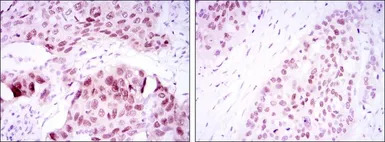

IHC-P analysis of lung cancer tissue (left) and esophageal cancer tissue (right) using GTX60381 SOX2 antibody [10F10].